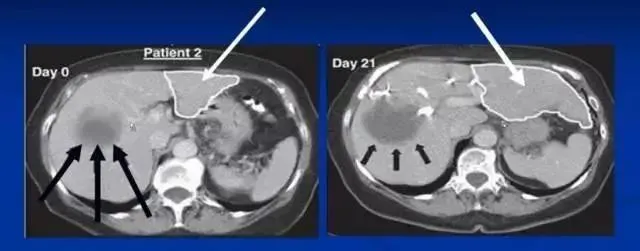

沈阳军区总医院消化内科郭晓钟等经股动脉肝内自体骨髓干细胞移植治疗肝硬化102例报告。

术后复查提示:

血浆蛋白改善在各项指标中最显著,其次为凝血功能的改善,可改善肝脏合成蛋白功能,对目前肝硬化腹水的患者具有积极意义。

第2个明显改善的指标为纤维蛋白原和凝血酶原时间,同样代表肝脏的合成功能提高。